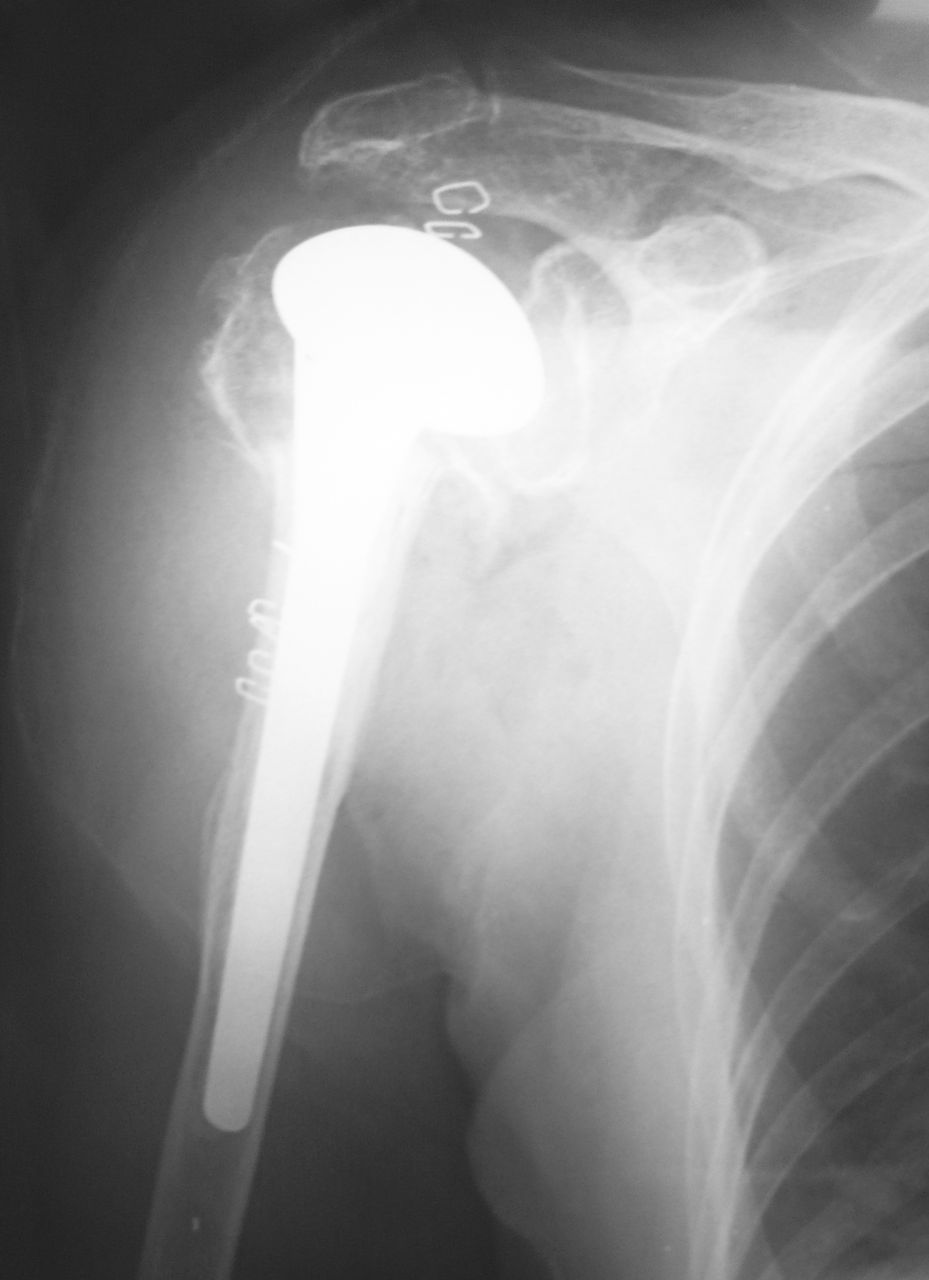

先日、高齢者の上腕骨近位端骨折(4 part骨折)に対して、右肩関節人工骨頭置換術(HHR)を施行しました。上腕骨関節面が翻転していたので、骨接合術の適応は無いと判断しました。

ここまでくると手術の山は越えたようなものです。 肩関節を伸展・外旋してリーミングおよびラスピングを施行してトライアルを行います。次にセメントなのですが、ここが少し曲者です。

一般的にはステム周囲にセメントを塗布してインプランテーションしますが、セメンティングが不充分なことが多いです。少しもったいないですが、セメントガンを用いる方が確実だと思います。

脱臼していないと信じるしかないですね(笑)。 一般的には肩関節の安定度はステムの後捻角に依存します。30度の後捻角がついていればまず安心してよいと思います。